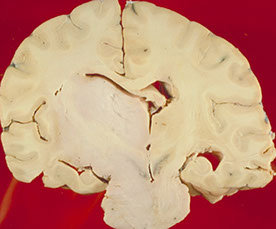

Glioblastoma multiforme (GBM)

More common in older pts (50's), involving the white matter

Imaging: heterogenous ring-enhancing mass with surrounding T2/FLAIR signal abnormality; if it crosses the midline, very likely to be a glioblastoma (butterfly lesion classic)

Micro shows an atypical infiltrative astrocytic glioma with frequent mits, pleomorphism, microvascular prolif and pseudopalisading necrosis

- either necrosis or microvasc prolif req'd for dx

- microvascular prolif is not an increase in the number of vessel spaces, but an increase in the thickness of the cellular coat of pericytes

-- thus to see microvasc prolif a smooth muscle actin (SMA) helps but a CD31 does not

Primary glioblastomas (de novo) occur in older pts, have EGFR amplification and/or PTEN mutations and have a very poor px

Secondary glioblastomas arise from a previous tumor that mutates and overexpresses p53, and has IDH1 mutations

- these have a slightly better px